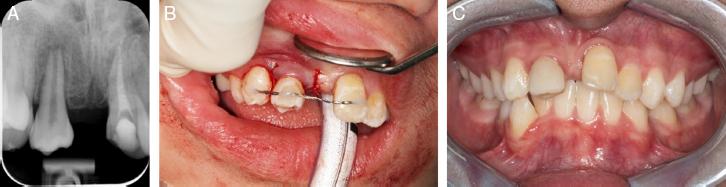

Figure 2.